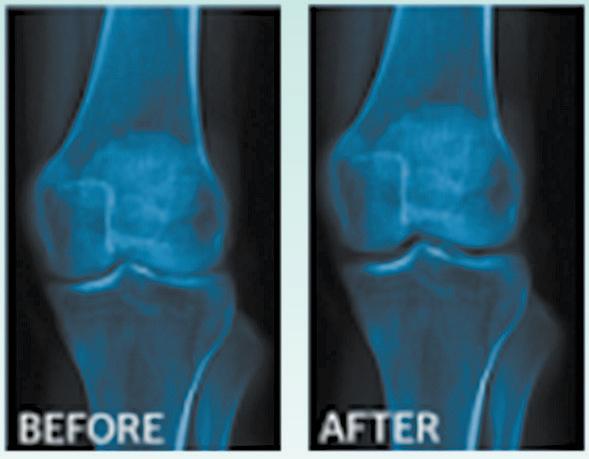

Dr. Cole will tell you about the latest methods, breakthroughs and time-tested strategies that will help you permanently and safely remove unwanted weight while quickly reclaiming your health, your youth and your life!

✔ Learn how Hormone Imbalances - man or woman - can distort your midsection into a large belly and prevent weight loss, even with dieting and exercise.

✔ Understand why “Counting Calories” doesn’t work, and the biggest mistakes people make with exercise that prevents weight loss.

✔ Clear approaches that inspire, are compatible with full lifestyles, and which show quick results with long-term success.

✔ Discover what really works for permanent loss of bulges and belly fat, safely and healthfully!

✔ Understand why prevention is key, what is necessary for “ageless” living well into our “senior” years. (NOW is the time!)

“I began my program with a goal of losing 45 pounds. I’ve not been hungry between meals (fortunately!) and I DO feel terrific! To date I’ve lost 27 pounds and 3 dress sizes. I started at a size 16 and am now a size 10 with some as small as size 8 and I’m not done. If you’ve not had success previously, Dr. Cole might be your answer! Don’t you owe it to yourself to sleep well, feel good and be healthy?”

-Linda Bacon Before After